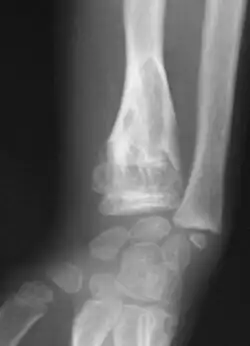

| X-ray image showing enchondromas localized in the lower part of the radius of a 7-year-old girl with Ollier disease. | |

X-ray showing enchondromas localized in the lower part of the radius of a 37-year-old patient affected with Ollier disease -